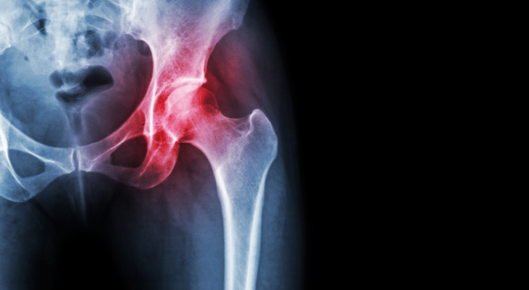

Joint with arthritis

Chiropractic Care for Osteoarthritis

Tired of living with osteoarthritis pain? Your chiropractor may be able to help.